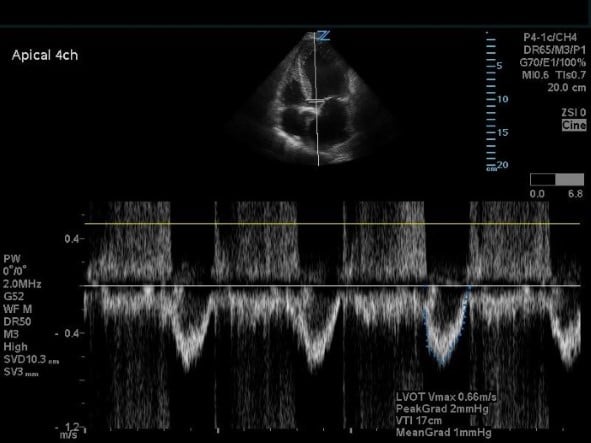

- Switch to pulse wave doppler (PWD) in the same A5CH view and place the doppler gate through the LVOT. Trace the obtained waveform in the same fashion to calculate the LVOT VTI. To also calculate cardiac output, measure the heart rate during this step using the machine preset.

Figure 6. Apical five-chamber view with pulse wave doppler on the LVOT.

- Utilize the report feature (can be machine-specific but often on machines with cardiac packages that will do calculations). The AV area, Vmax, and mean transaortic gradient will be displayed.

An AV area <1.0 cm2, peak aortic velocity >4 m/s, mean transaortic gradient >40 mmHg is diagnostic for critical AS, however, in cases of depressed ejection fraction, AV area <1.0 cm2 can be the only abnormal parameter.7